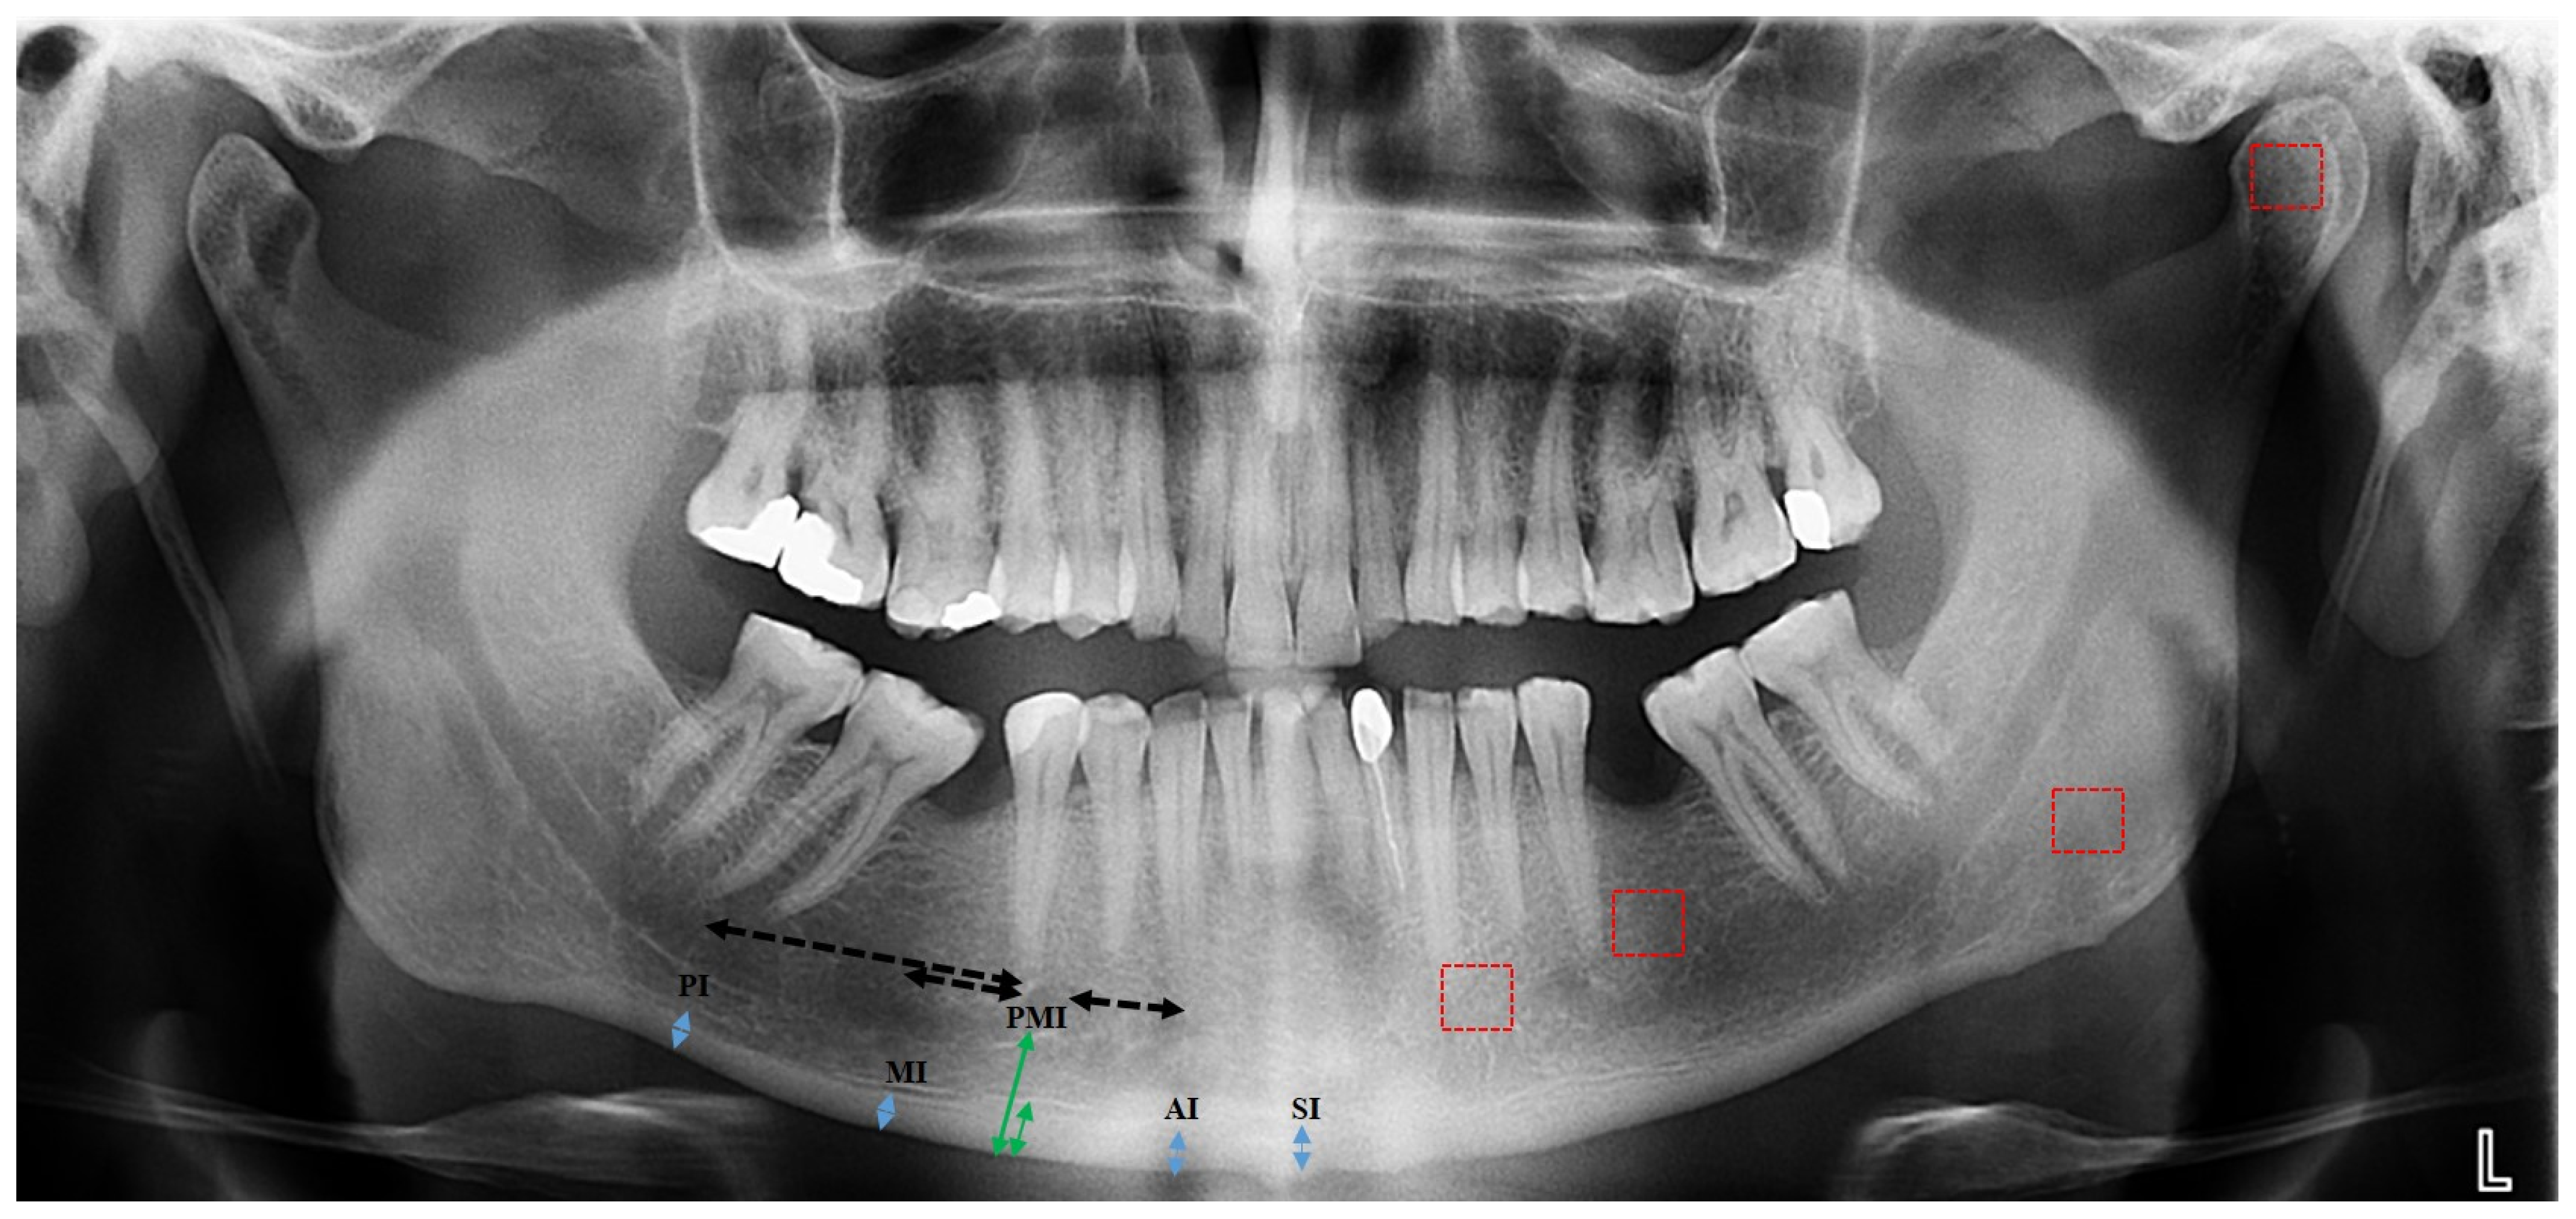

2.2. Measurements

2.2.2. Radiomorphometric Analysis